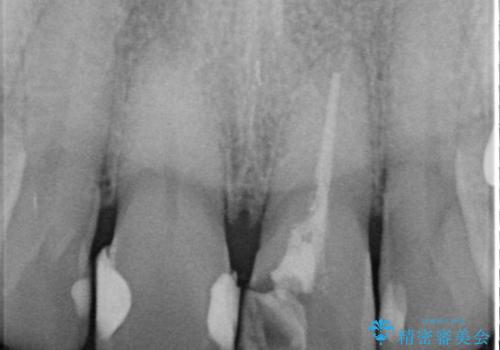

- 歯髄が死んで変色していた歯に対して、根管治療とオールセラミッククラウンでの修復を行いました。まず、根管治療で内部の感染を除去し、歯の強度を高めるためにファイバーコアを装着しました。その後、審美性と耐久性を考慮し、オールセラミッククラウンで覆うことで、自然な歯の色合いに近い美しい仕上がりを実現しました。

歯髄が死んだ歯は通常の健康な歯に比べて透過性が低く、特有の暗い色調を帯びる傾向にあります。変色は時間とともに進行し、薄い茶色や灰色、黄色がかった色合いになることが多いです。このような変色は、審美的な面で気になる場合が多く、オールセラミッククラウンなどでの修復が行われることも一般的です。